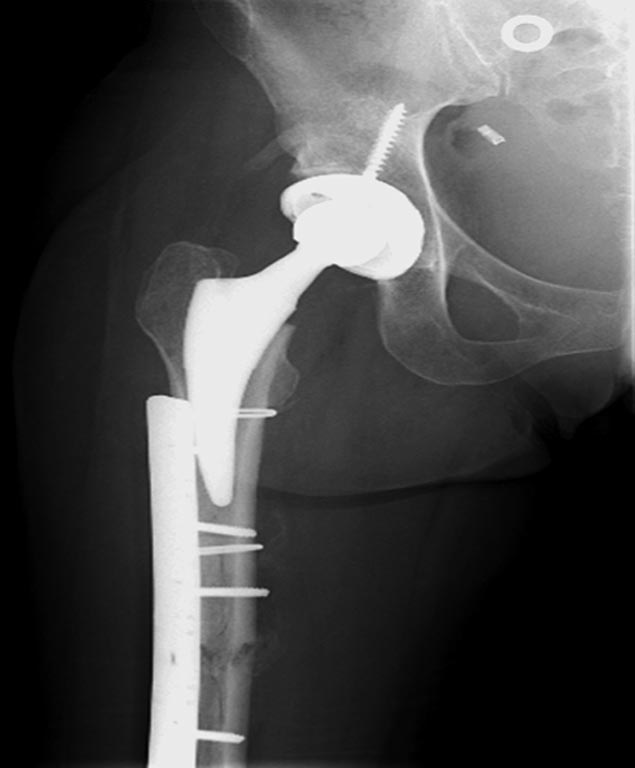

На 25 день с момента травмы операция на Jackson table с боковым обширным

доступом. Удаление стержней с местной обработкой. В тазобедренном

суставе удаление головки, на дне вертлужной впадины полная отслойка

хряща. Вертлужный компонент с одним винтом и короткая ножка -  Fitmore

press fit stem. На второй день однократно доза радиации для профилактики

гетеретопической оссификации.  Послеоперационный период без температуры.

Выписана. Нагрузку разрешили на левой стороне, а полная в 3 мес.  Здесь

снимки при амбулаторном наблюдении​: послеоперационно, 2 мес, 3 мес и 6

мес. Нагрузка полная, отсутствует хромота, и нет жалоб.